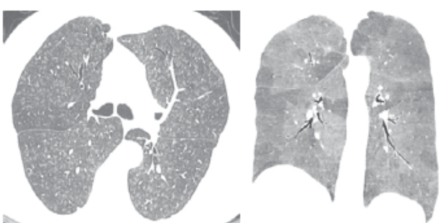

病例:这位患者表现为马赛克灌注(Mosaic perfusion),与马赛克影的相同点是都出现在吸气相CT,而马赛克灌注是指的在正常密度的肺脏下,吸气相CT看到了一些低密度区,这些低密度区这提示血管或气道疾病,提示血管减少、气体陷闭。

同时我们看到患者还伴有小叶中央型的磨玻璃样结节,可见吸气相(下图左)和呼气相(下图右)是有明显差别的。